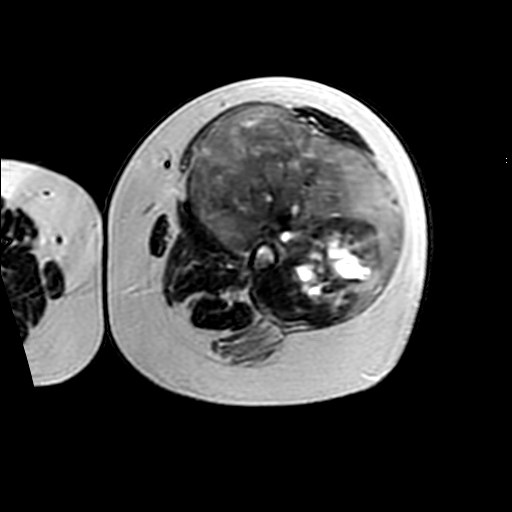

左侧大腿外伤10余年,当时情况不清,发现左侧大腿肿胀7年余,而后又有多次外伤史,近1年来出现疼痛,减重半年。查体:左侧大腿肿胀明显,皮温、肤色正常。

增强

软组织肿块,股骨破坏,增强不均匀强化-----支持恶性肿瘤